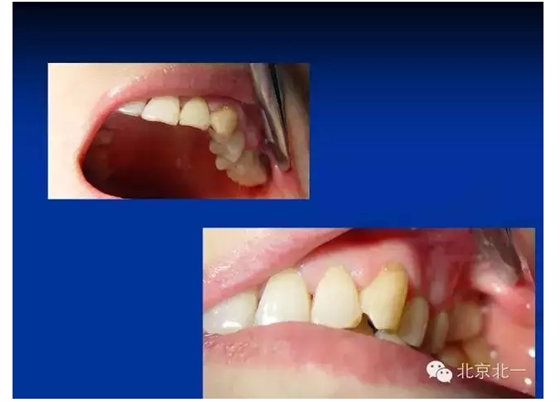

往屆精彩剪影